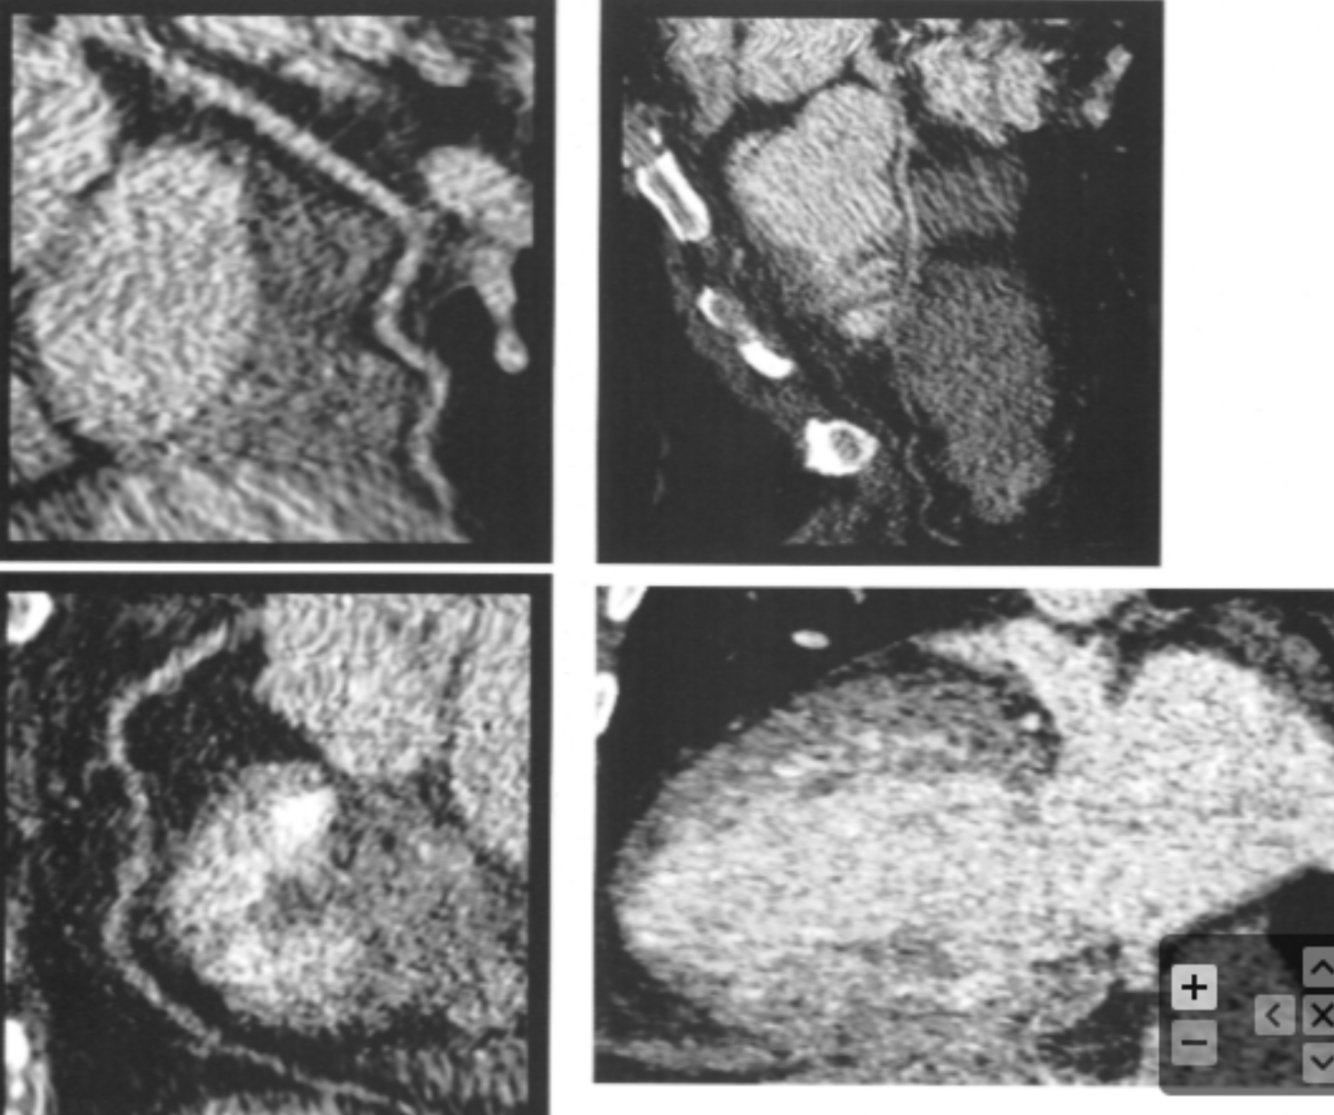

Describe the findings:

Beam Hardening Artifact